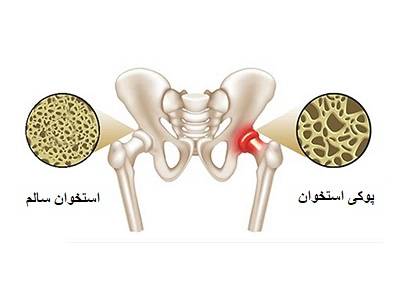

۲۴ مهر ۱۴۰۳هفته سلامت بانوان

۲۴ مهر ۱۴۰۳